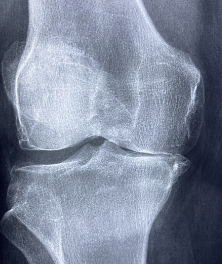

글루코사민 콘드로이친 msm 효능 및 부작용 적정섭취량 등 관련 정보 알아보도록 하겠습니다. 관절은 뼈와 뼈 사이에 위치한 연결점으로, 우리 몸을 움직이기 위한 중요한 부분입니다. 관절은 뼈의 끝에 위치한 연골과 뼈를 연결하는 인대로 이루어져 있으며, 이러한 구조는 원활한 움직임을 가능하게 합니다. 하지만 연령이 들어가거나 부상 등으로 인해 관절의 기능이 손상되면 관절염과 같은 질환으로 발생할 수 있습니다. 이러한 질환은 관절 통증, 감각 이상, 염증 및 손상 등을 일으키며, 일상생활에서의 움직임과 활동에 지장을 주어 생활의 질을 저하시킵니다. 이에 따라 적절한 치료와 예방이 필요하며, 영양소와 운동 등을 통한 관리가 중요합니다.

글루코사민은 연골을 유지하는 데 필요한 성분으로, 연골 조직의 생산과 수리를 돕습니다. 또한 관절염 등의 관절 질환으로 인한 통증 및 염증을 완화하는데도 효과적입니다. 또한 연골 조직의 건강을 유지함으로써, 무릎 퇴행성 질환의 발생을 예방하고 뼈 건강에도 도움을 줄 수 있습니다.